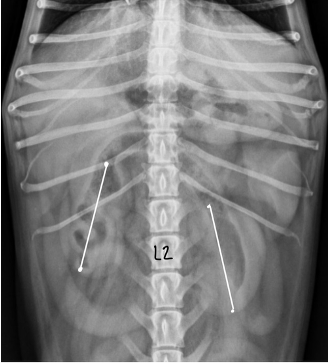

dog kidney size vs cat kidney size

dog - 2.5-3.5 x length L2

cat - 1.9-3.2 x length L2